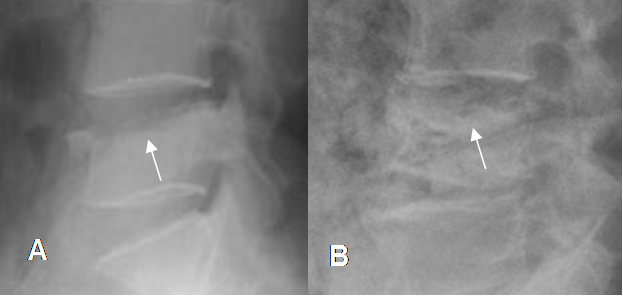

Fig 215. Fractura crónica.

A, B y C: Rx lateral. Diferentes grados de pérdida en la altura vertebral, conservándose la densidad de los cuerpos y la nitidez de la placa terminal superior, por fracturas de evolución crónica.